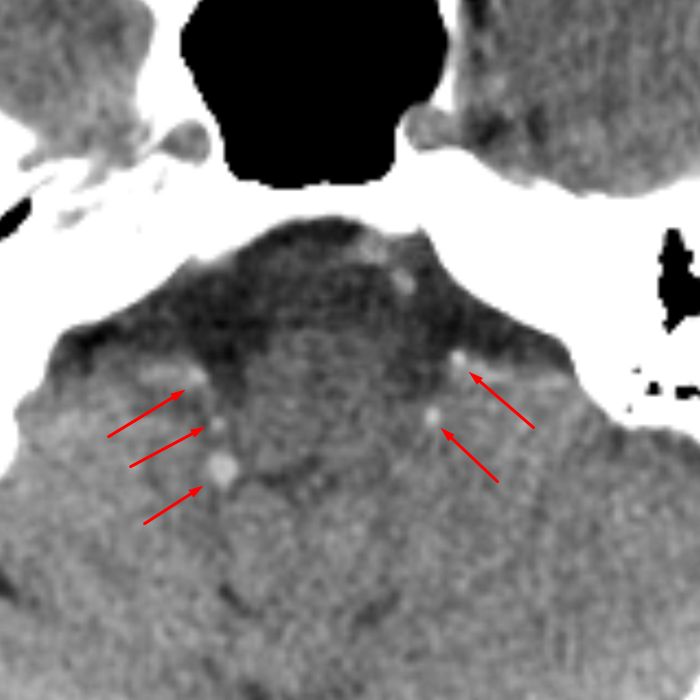

Age: 41

Sex: Male

Indication: Trauma